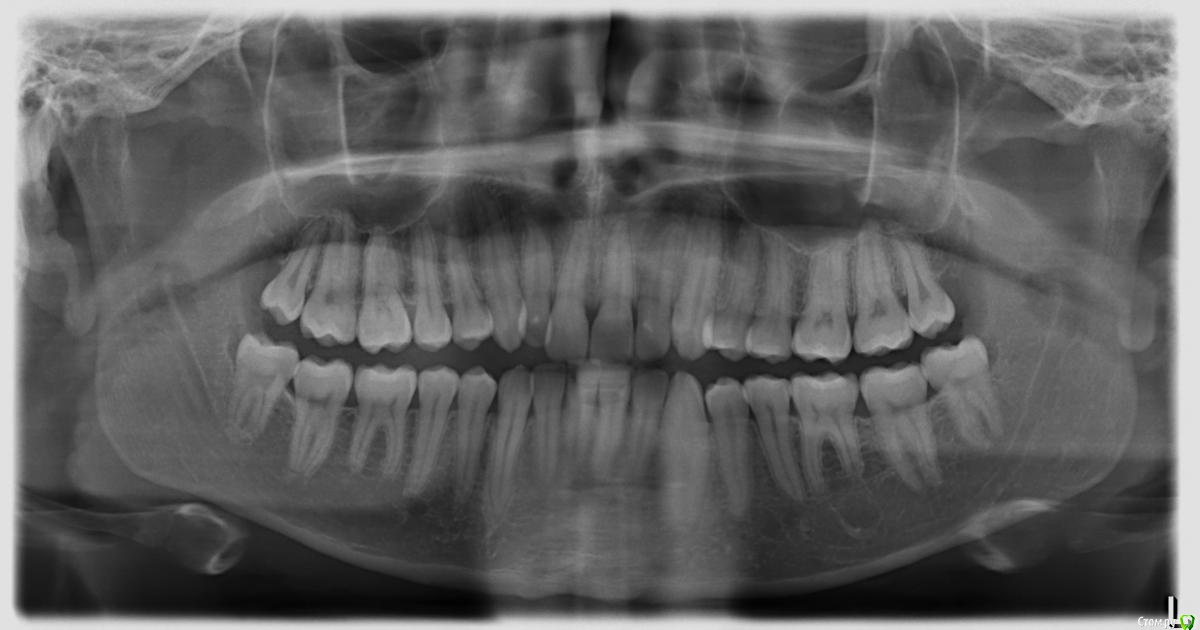

Alex999 Опубликовано 16 апреля, 2019 Поделиться Опубликовано 16 апреля, 2019 (изменено) Здравствуйте! Ничего особо не беспокоит кроме скученности зубов. Посмотрел свой снимок возникли вопросы.Эта правда, что судя по снимку, корни зубов 17 26 и 27 вышли из кости и упираются в слизистую пазухи? Хотя тьфу-тьфу-тьфу пока ничего не беспокоит.У 48 и 38 вроде есть небольшое рассасывание кости у свода челюсти.Нет ли кист у зубов нижней челюсти. Вроде что-то такое наблюдается, но на кисту не похоже. Может структура кости такая. Спасибо. Изменено 16 апреля, 2019 пользователем Alex999 Ссылка на комментарий

АнтонТЛТ Опубликовано 16 апреля, 2019 Поделиться Опубликовано 16 апреля, 2019 Между корнями и слизистой пазухи есть тонкая прослойка костной ткани.Кист нет.38 и 48 пользоваться ирригаторов и наблюдать, если начнет воспаляется за ними, то их лучше удалить вместе с 18 и 28. 2 Ссылка на комментарий